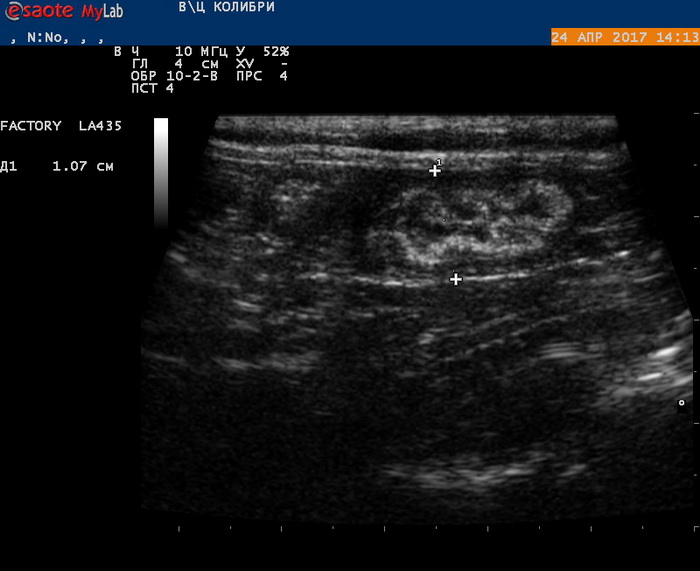

Внешние признаки для определения беременности очень ненадежны. Поэтому очень важно подтвердить раннюю беременность, если есть подозрение на преждевременное прерывание беременности. У кошек диагностика беременности с помощью УЗИ может быть информативной уже на 16-18 день, но это во многом зависит от прибора и врача.

Подавляющее большинство таких недугов можно обнаружить только с помощью ультразвуковой диагностики.